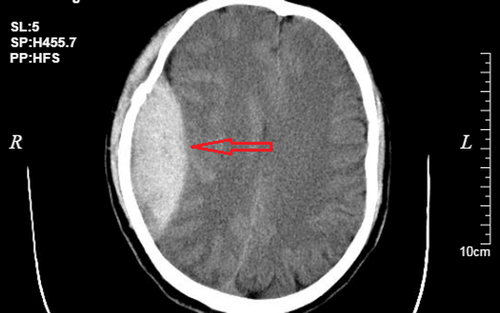

Điều trị hút máu tụ dưới màng cứng có ảnh hưởng đến trí nhớ không?

Cho em hỏi, điều trị hút máu tụ dưới màng cứng có ảnh hưởng đến trí nhớ không ạ? Nếu có ảnh hưởng thì có cách nào giúp bệnh nhân điều trị và phục hồi tốt nhất không ạ? Mong bác sĩ tư vấn giúp em. Em xin chân thành cảm ơn.